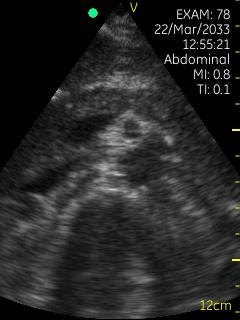

Vscan临床图片 腹部